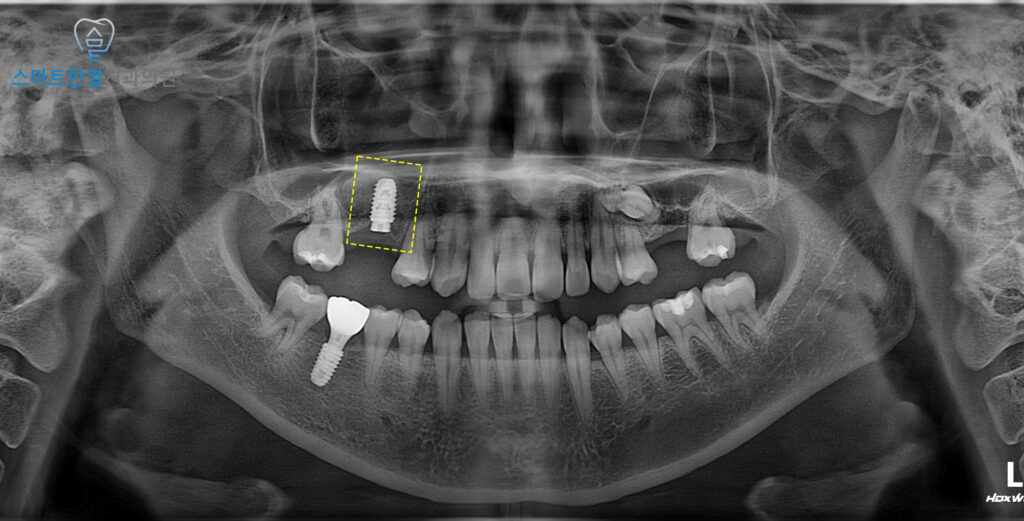

파노라마 사진을 촬영해 보니,

인접면으로 충치가 생겨

치아 뿌리 쪽까지

이어진 상태였는데요.

이 정도로 진행된 충치는

단순한 재치료로는

예후를 기대하기 어렵기 때문에,

장기적인 구강 건강을 위해

발치를 고려할 수밖에 없는

상황이었답니다.

25.01.22 / 25.09.06

화서동치과 스마트한결치과의

임플란트 수술 전후 사진이에요.

환자분께서는 충치가 심한 치아뿐만아니라

미맹출되어있는 치아쪽으로

관리가 힘들었는데

두 치아를 함께 해결할 수 있어서

다행이라며 만족해 주셨어요.